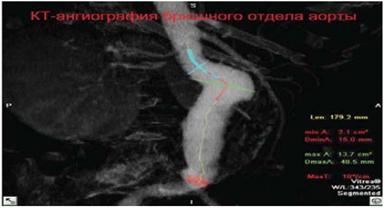

Рисунок 4.2 - Измерение диаметра просвета пораженного отдела брюшной аорты.

Виртуальная КТ-ангиография позволяет обнаружить потенциальные причины острой ишемии, такие как артериальный стеноз высокой степени, изъязвление бляшки или аневризму с частичным тромбированием, что позволяет предпринять тромболитическую терапию или отказаться от тромболитической терапии (рис.18-20).